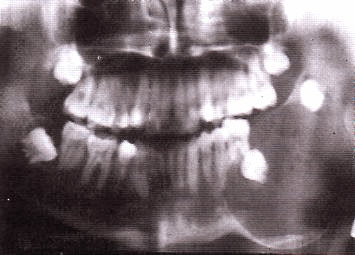

Рентгенологическая картина

Возможны следующие варианты амелобластомы:

1. Ряд округлых полостей.

2. Одна костная полость, окруженная множеством более мелких полостей.

3. Ряд округлых полостей, в 1-2 из которых заключен зубной фолликул или сформированный зуб.

4. Многоугольные полости.

5. Крупнопетлистая структура кости за счет множества мелких кист.

6. Несколько единичных крупных кистозных полостей.

7. Одна большая кистозная полость с неровными краями.

8. Одна большая полость, в которую обращены корни зубов (напоминает радикулярную кисту).

9. Одна большая киста, в которую обращена коронковая часть непрорезавшегося зуба. Этот вариант напоминает фолликулярную кисту.

Важнейшей рентгенологической чертой адамантином является различная степень прозрачности тени полостей особенно четко выраженной в поликистозных адамантиномах. Центральные отделы кистозных полостей прозрачнее, чем краевые. В однокамерных адамантиномах удается видеть полоску полутени вдоль костных границ опухоли. Нередко отмечается резорбция корней зубов в области опухоли.